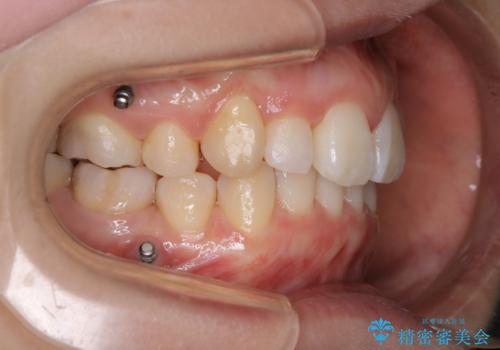

- 全体的に着色が付いているのが気になるとのことで来院されました。

PMTC60分コースを行いました。

着色がかなり頑固なため、エアフローも使い着色を除去していきました。

下の前歯にはかなり多くの歯石が付いており、デンタルフロスでもう少し防げるため、使用法や頻度を確認しました。

インビザラインの矯正治療は、マウスピースの使用時間が少ないとマウスピースと歯のフィッティングが悪くなりシュミレーション通りに歯が動かなくなるため、追加アライナーといって、再度スキャニングを行い新しいフィットの良いマウスピースに変えていきます。そのスキャニング時にアタッチメント(歯の表面に付いた突起)も除去するため、そのタイミングでクリーニングするのもおすすめです。